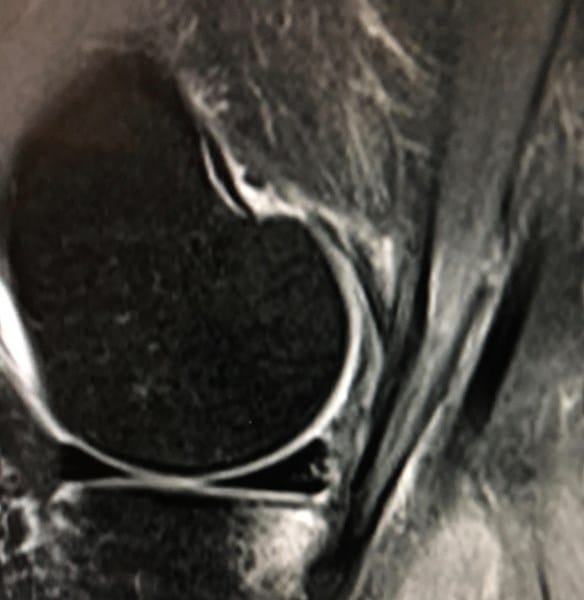

¿Es posible que tenga una Rotura de LCA o menisco?

Hace más de un mes me lesioné esquiando y todavía no sé los resultados de la resonancia, sólo he podido ver las imágenes... Tengo la rodilla bloqueada en 10-90 grados y dolor intermitente, a penas puedo caminar.. Podría ser el ligamento, ¿el menisco o ambas?